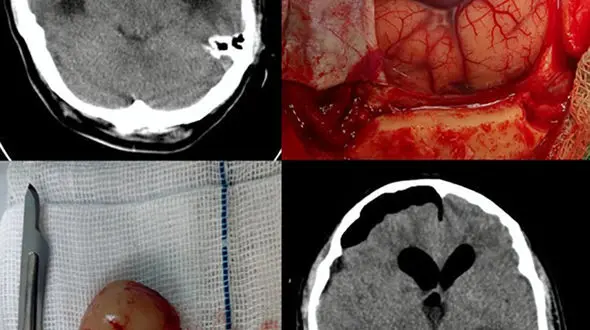

حوادث رکنا : عمل جراحی میکروسکوپی یک مرد 37 ساله در لامرد با موفقیت انجام شد.